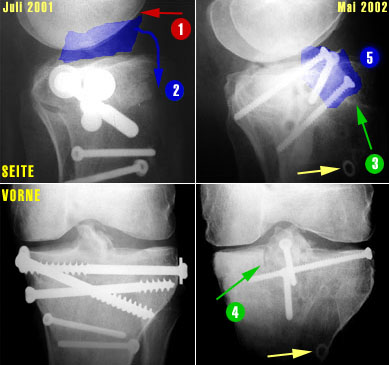

Und so sieht das ganze radiologisch aus (links die Bilder vom Juli 2001 mit den 5 alten Schrauben, rechts die Bilder vom Mai 2002 mit den 3 neuen Schrauben - auf die Bildfragmente klicken, um eine grössere Fassung des Ausschnittes zu sehen).

Hier klicken für grössere Fassung dieses BildteilsHier klicken für grössere Fassung dieses BildteilsHier klicken für grössere Fassung dieses BildteilsHier klicken für grössere Fassung dieses Bildteils

1. Das Problem, Bild links oben: Die zu hoch eingewachsene Eminenz (im Kniegelenk höchster Teil des Schienbeins, blau eingefärbt) verhindert die Streckung, weil sie am Oberschenkel anstösst, wenn das Bein gestreckt werden sollte (1).

2. Die Lösung: Weil an der Eminenz Bänder angewachsen sind, kann man das zu hoch stehende Fragment nicht einfach abhobeln - man muss es nach unten ziehen (2). Dafür muss aber zuerst Platz geschaffen werden...

3. Die Ausführung: Am Schienbein werden diverse Schnitte vollzogen. Im Bild rechts oben (3) ist der Schnitt von vorne sichtbar, im rechten unteren Bild (4) ein Schnitt von oben. Aus dem Schienbein ein Keil entfernt, sodass die zuerst von überschüssigen Knochenfragmenten befreite Eminenz gewissermassen nach vorne und unten ins Schienbein geklappt werden und mit drei Schrauben festgemacht (5) werden kann. In den unteren beiden Bildern ist auch schön sichtbar, dass die Eminenz nun wieder eine normalere Form hat.

Schön sichtbar sind auch die alten Löcher der im November 2001 entfernten Schrauben sowie in den Bildern rechts (gelbe Pfeile) eine alte Unterlagsscheibe, die während dem Sommer 2001 im Knochen festgewachsen war und im November nicht herausgefischt werden konnte (auf die Bildfragmente klicken, um eine grössere Fassung des Ausschnittes zu sehen).

Die neue Konstruktion von vorne bei ca. 45° gebeugtem Knie. Rechts von der Eminenz ist einer der frischen Schnitte im Knochen sichtbar.